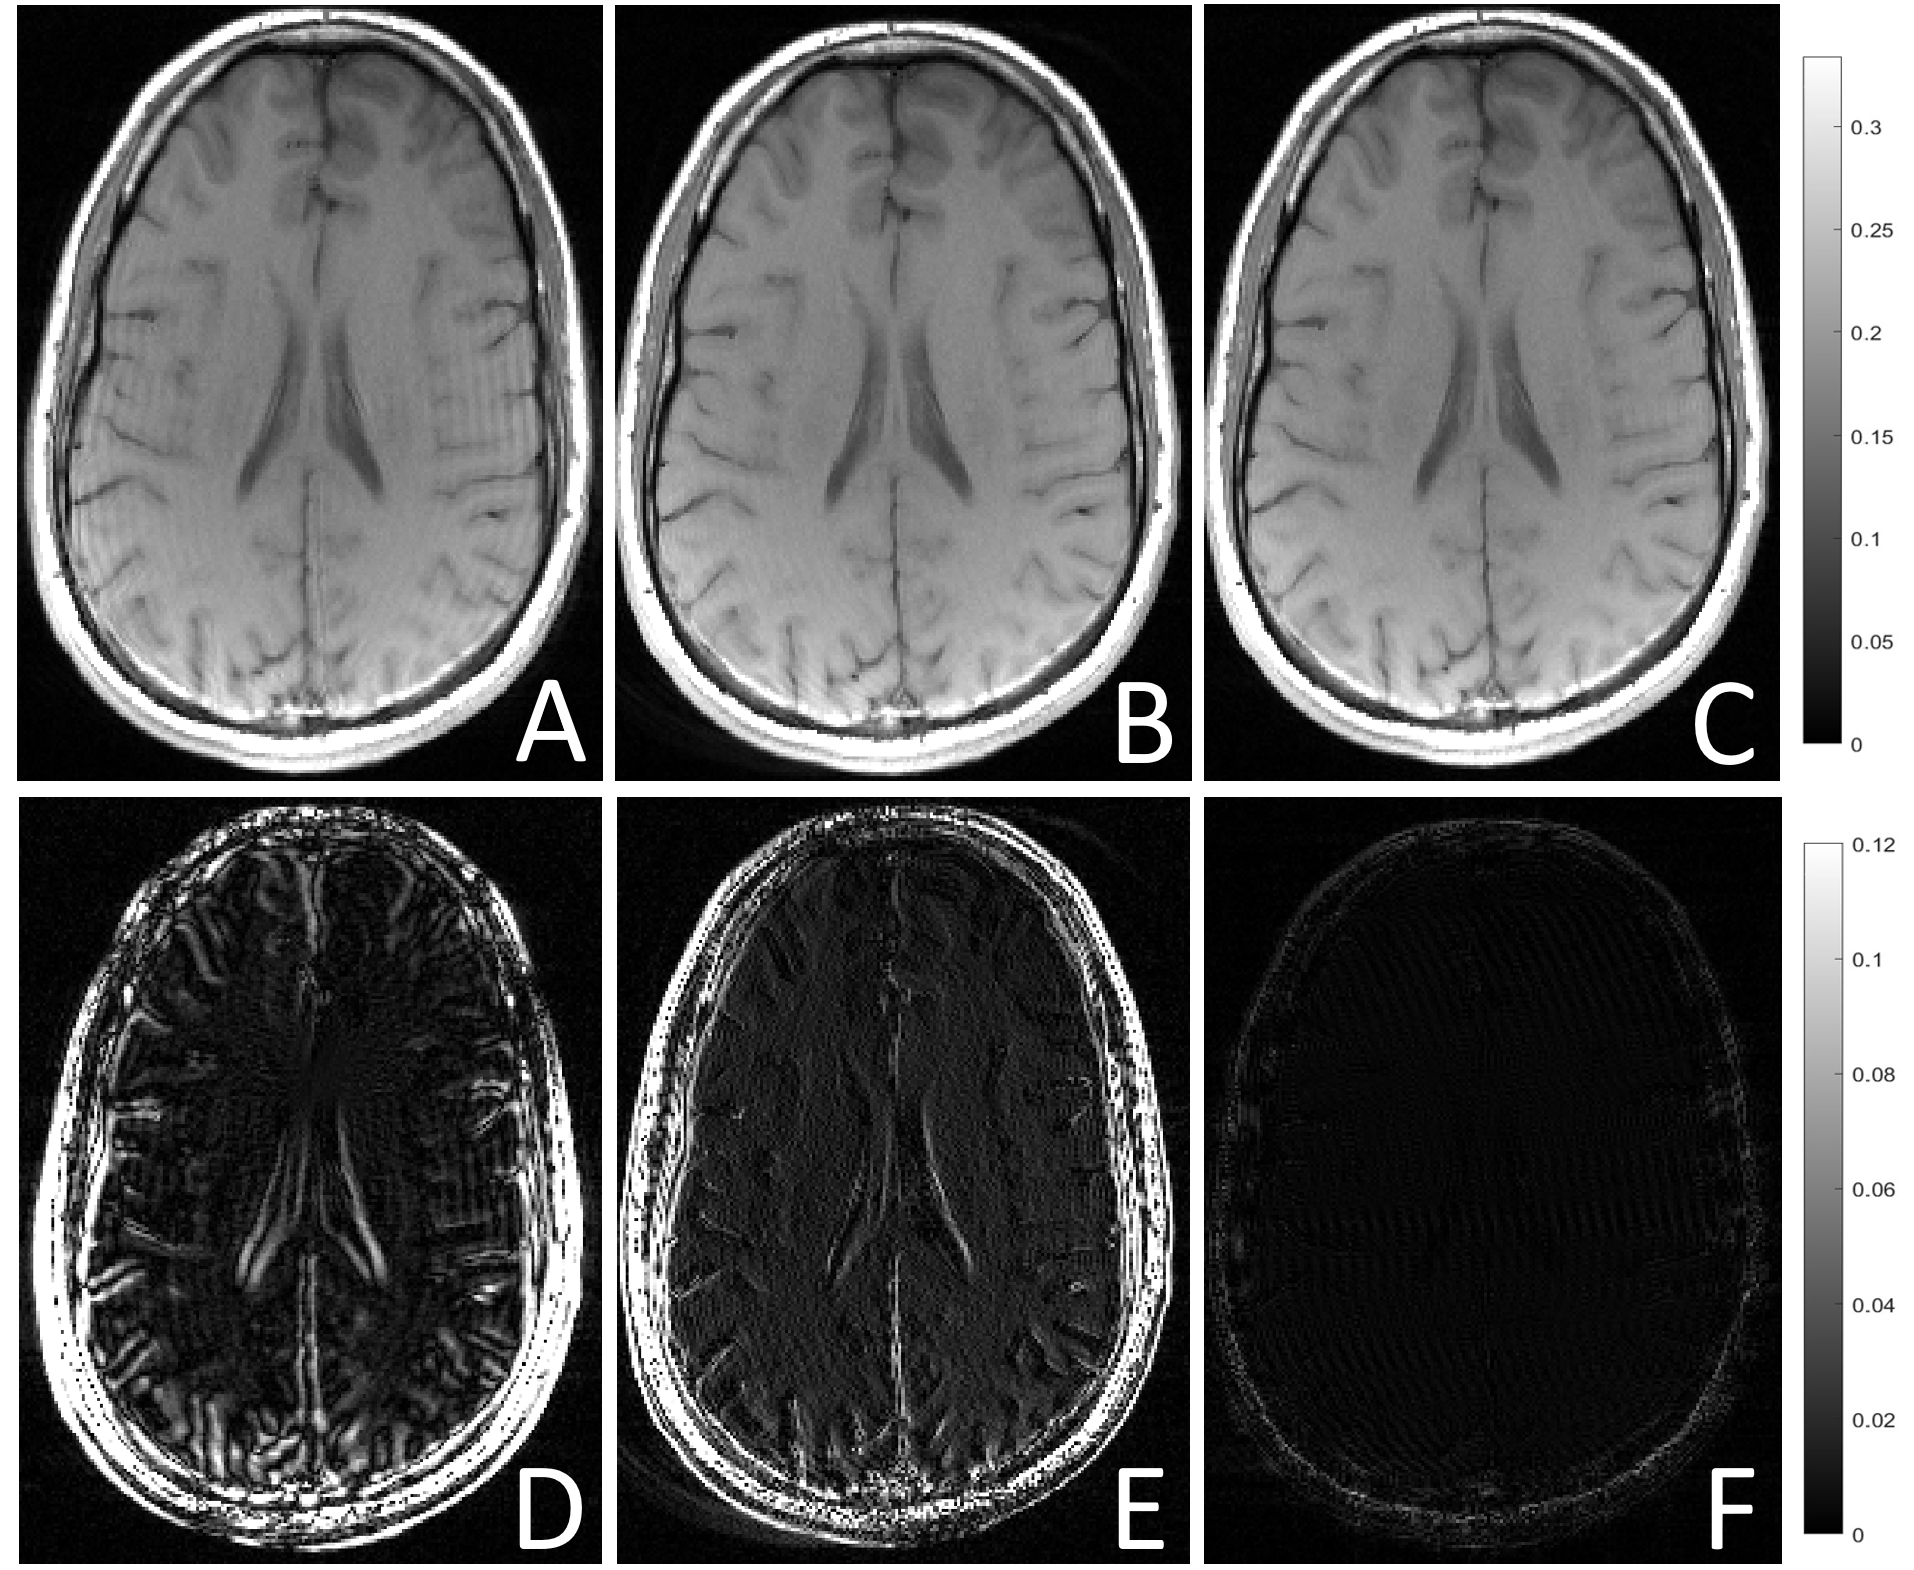

3.0.3 Motion correction from DNN predictions

The last stage of the pipeline entails reversing the effects of motion using a model-based approach by building a NUFFT matrix from the estimated rotation angles following phase ramp cancellation with the formula in Equation 7. Qualitative results for simulations are shown in 8a and are also compared to the GradMC method. Quantitative results presented as boxplots for a range of angles and PE lines covering different motion intensities and k-space regions are shown in 8b and 8c. NUFFT reconstructions with SISMIK estimations result in a median PSNR of 37.8 dB and a median SSIM of 0.98. For the same slices corrected with GradMC, a median PSNR of 29.7 dB and SSIM of 0.93 are obtained.

By only focusing on the ”Corrupted” and ”SISMIK” boxplots in Figure 8 (b) and (c), we can compare the PSNR and SSIM metrics of corrupted and restored slices, solely from SISMIK estimations, with respect to the motion-free ground truth used for simulation. All the restored slices obtain a PSNR >> 30 dB, whereas all the corrupted ones are below 30 dB. For the SSIM metric, all corrupted slices are below 0.91 and all the restored ones (except for a few outliers) are above 0.97. Overall, this demonstrates that the proposed DNN estimations allow a model-based restoration with NUFFT that can completely separate the motion-corrupted PSNR and SSIM distributions from the restored ones.

Refer to caption

(a)

(b)

(c)

Figure 8: (A) Representative example of simulated corruption (approx. 3 degrees rotation). (B) Restored with GradMC. (C) Restored with NUFFT from DNN predictions. (D,E,F) are the absolute difference to the reference motion-free acquisition used for simulation. PSNR and SSIM distributions for simulations over a range of [-4°, 4°] for different subjects and slices as shown In boxplots (b) and (c). In (b) the performance of SISMIK is compared to the GradMC method. In (c) we can observe that the distributions of PSNRs and SSIMs of the corrupted and restored (both with SISMIK) slices, do not overlap.

A comparison with the GradMC model-based method[21] was performed. The latter uses an ”autofocusing” approach based on the optimization of an entropy metric to estimate motion parameters of a corrupted MRI acquisition. Figure 8 shows that the proposed DNN’s estimations of the motion parameters followed by phase cancellation and iterative NUFFT achieves a higher increase in PSNR and SSIM. GradMC is also less robust in the sense that it can often diverge and is unable to find the optimal motion parameters. For this comparison, GradMC was initialized with motion parameters obtained from the DNN, in order to avoid a divergent behaviour. This highlights the fact that such autofocusing approaches can benefit from better initialization. The proposed DNN can provide these estimations and therefore reduce the computational burden of such iterative methods, which may require in the order of minutes to correct a single slice.

Figure 8 also shows that the PSNR and SSIM distributions of motion corrupted and restored images are consistent and do not overlap after motion estimation and reconstruction with the proposed approach, showing improvement in all simulations.